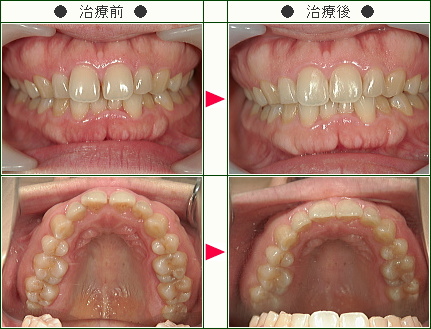

前歯のすきっ歯矯正の治療症例解説(20歳から39歳まで)--部分矯正--その2

☆前歯のすきっ歯矯正症例[竹内様 26歳 女性]